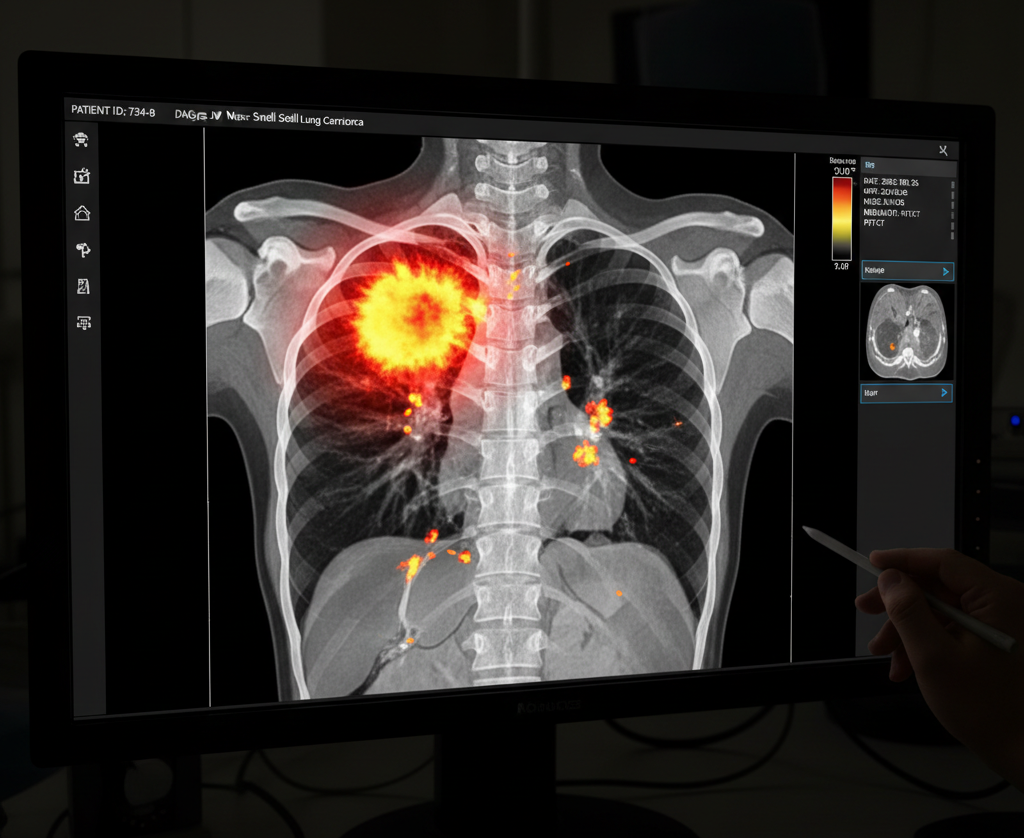

• Medical Imaging: This is where AI has made its most visible mark. Algorithms can analyze thousands of radiology images like mammograms, CT scans, and MRIs in seconds, flagging suspicious abnormalities that might be missed by the human eye.

The true value of this technology lies in the creation of a symbiotic relationship between clinician and algorithm. Human experts, such as radiologists, face enormous workloads and the challenge of “interobserver variability,” where different specialists may draw different conclusions from the same image. AI excels at the tireless, data-intensive task of initial analysis, providing a consistent and rapid first pass that reduces variability and flags areas of concern.

This is why AI can sometimes identify patterns that are “invisible to the human eye”. It is not just mimicking how a radiologist thinks; it is discovering new, data-driven ways of seeing the image, which explains its potential to sometimes outperform human experts on specific, narrow tasks. Several well-known CNN architectures, such as VGG16, ResNet50, and AlexNet, are frequently cited in cancer detection research for their proven effectiveness.